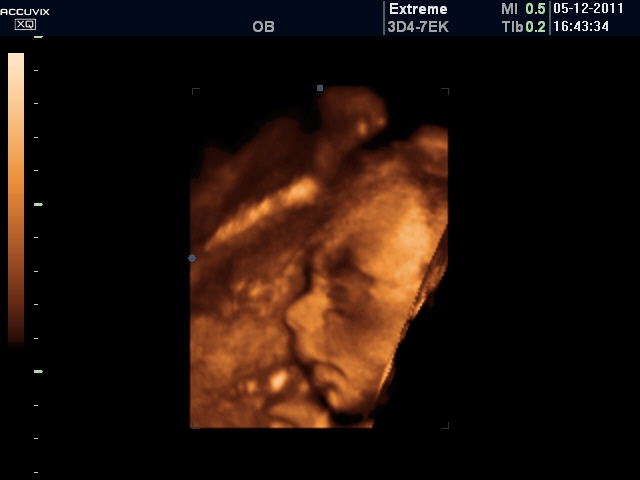

25+5 ahoj holky, tak sem byla včera na 4D uz, bylo to moc fajn, akorát se teda kubík rozhodl, že se nám pořádně neukáže, tak ho máme jenom z profilu...skoro celou dobu měl před obličejem ručičku, potom dokonce i patičku...:) vtipný...:) jinak pan doktor včera říkal, že už je otočený hlavičkou dolů, to prostě udělal to schválně..ještě minulé pondělí byl krásně hlavou nahoru a koukal se na nás...:) každopádně je moc krásnej...:)

MARU, moc gratuluju k obrázku. Kubík bude krasavec! Úplně Ti takovýhle obrázek závidím. My jsme to zkusili 2krát a ani jednou jsme nebyli úspěšní. Poprvé měla holčička přes obličej ručičku a v té poloze následně i usnula a podruhé měla hlavu zabořenou v placentě, tak nebylo vidět už vůbec nic

Maru to je opravdu krásné miminko, to už je malý človíček

, to je úplně neuvěřitelný, že po 26 týdnech máme v bříšku takové drobečky

. Už se moc těším na náš ultrazvuk, jdeme příští týden, doufám, že se nám miminko nebude schovávat.